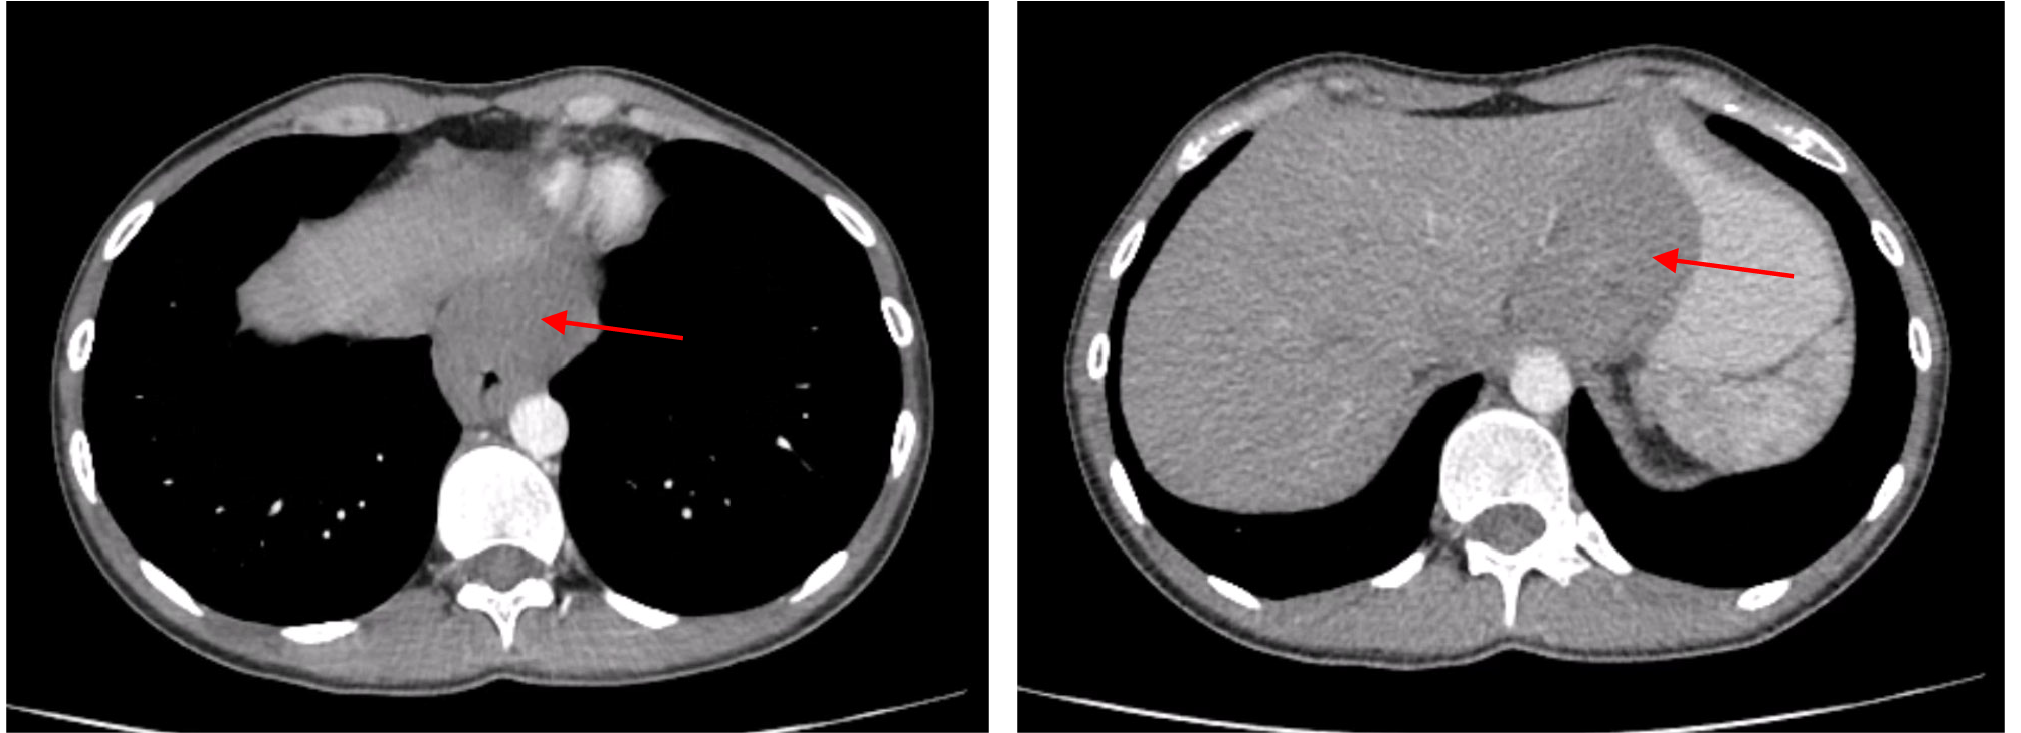

Endoscopic examination revealed a polypoid, elastic, mobile lesion approximately 3 cm in diameter, located 32 cm from the incisors. The overlying mucosa appeared intact.

A barium swallow demonstrated a round filling defect on the posterior wall of the lower third of the esophagus, measuring 39×29 mm, with well-defined margins and intramural calcifications. Contrast-enhanced CT of the chest, abdomen, and pelvis showed a well-circumscribed lesion measuring 25×22×30 mm in the middle third of the esophagus, narrowing the esophageal lumen to a slit-like configuration. The external contour of the esophageal wall remained intact (Fig. 8a).

Due to its size and location, enucleation was deemed technically feasible. Thoracoscopic enucleation of the esophageal leiomyoma was performed. A mucosal defect occurred at the site of the prior endoscopic biopsy and was closed with interrupted sutures. The right pleural cavity was drained via the seventh intercostal space.

On postoperative day (POD) 1, the patient was diagnosed with esophageal perforation complicated by mediastinitis. Leakage was confirmed by assessing drain output after oral administration of a contrast dye. CT imaging of the chest, abdomen, and pelvis revealed signs of esophageal wall perforation. Endoscopic clipping and esophageal stent placement were performed, and a nasojejunal feeding tube was inserted for enteral nutrition. On POD 6, fluid collections in both pleural cavities were drained under ultrasound guidance. Follow-up endoscopy on POD 7 revealed a persistent esophageal wall defect with dense fibrin deposition above the stent. By POD 10, granulation tissue formation was observed at the defect site. On POD 18, CT imaging revealed an isolated esophago-atmospheric fistula extending to a drainage tract through the sixth intercostal space on the right. The stent was removed, and the esophageal defect had decreased to 7 mm. Endoscopic vacuum therapy (EVT) was initiated under general anesthesia. On POD 21, the EVT system was replaced and subsequently removed on POD 23. Fistulography was performed, followed by thrice-daily irrigation of the fistulous tract with antiseptic solutions. Daily drainage from the mediastinum amounted to approximately 85 mL of serous, saliva-mixed exudate. The drain was connected to a pleural aspirator. The patient received enteral feeding with 1000 mL of nutritional formula and 1500 mL of water per day. At discharge on POD 64, the patient was in satisfactory condition. He was afebrile, communicative, and reported no significant complaints. Sutures had been removed, and surgical drains remained in place and functional. The patient was transferred to a military hospital for continuation of care until complete closure of the esophago-atmospheric fistula.

Complications included esophageal perforation, bilateral lower-lobe hospital-acquired pneumonia, external esophagocutaneous fistula, and mediastinitis.

Pathology: a benign esophageal leiomyoma was identified, measuring 3.0×2.0×1.5 cm.